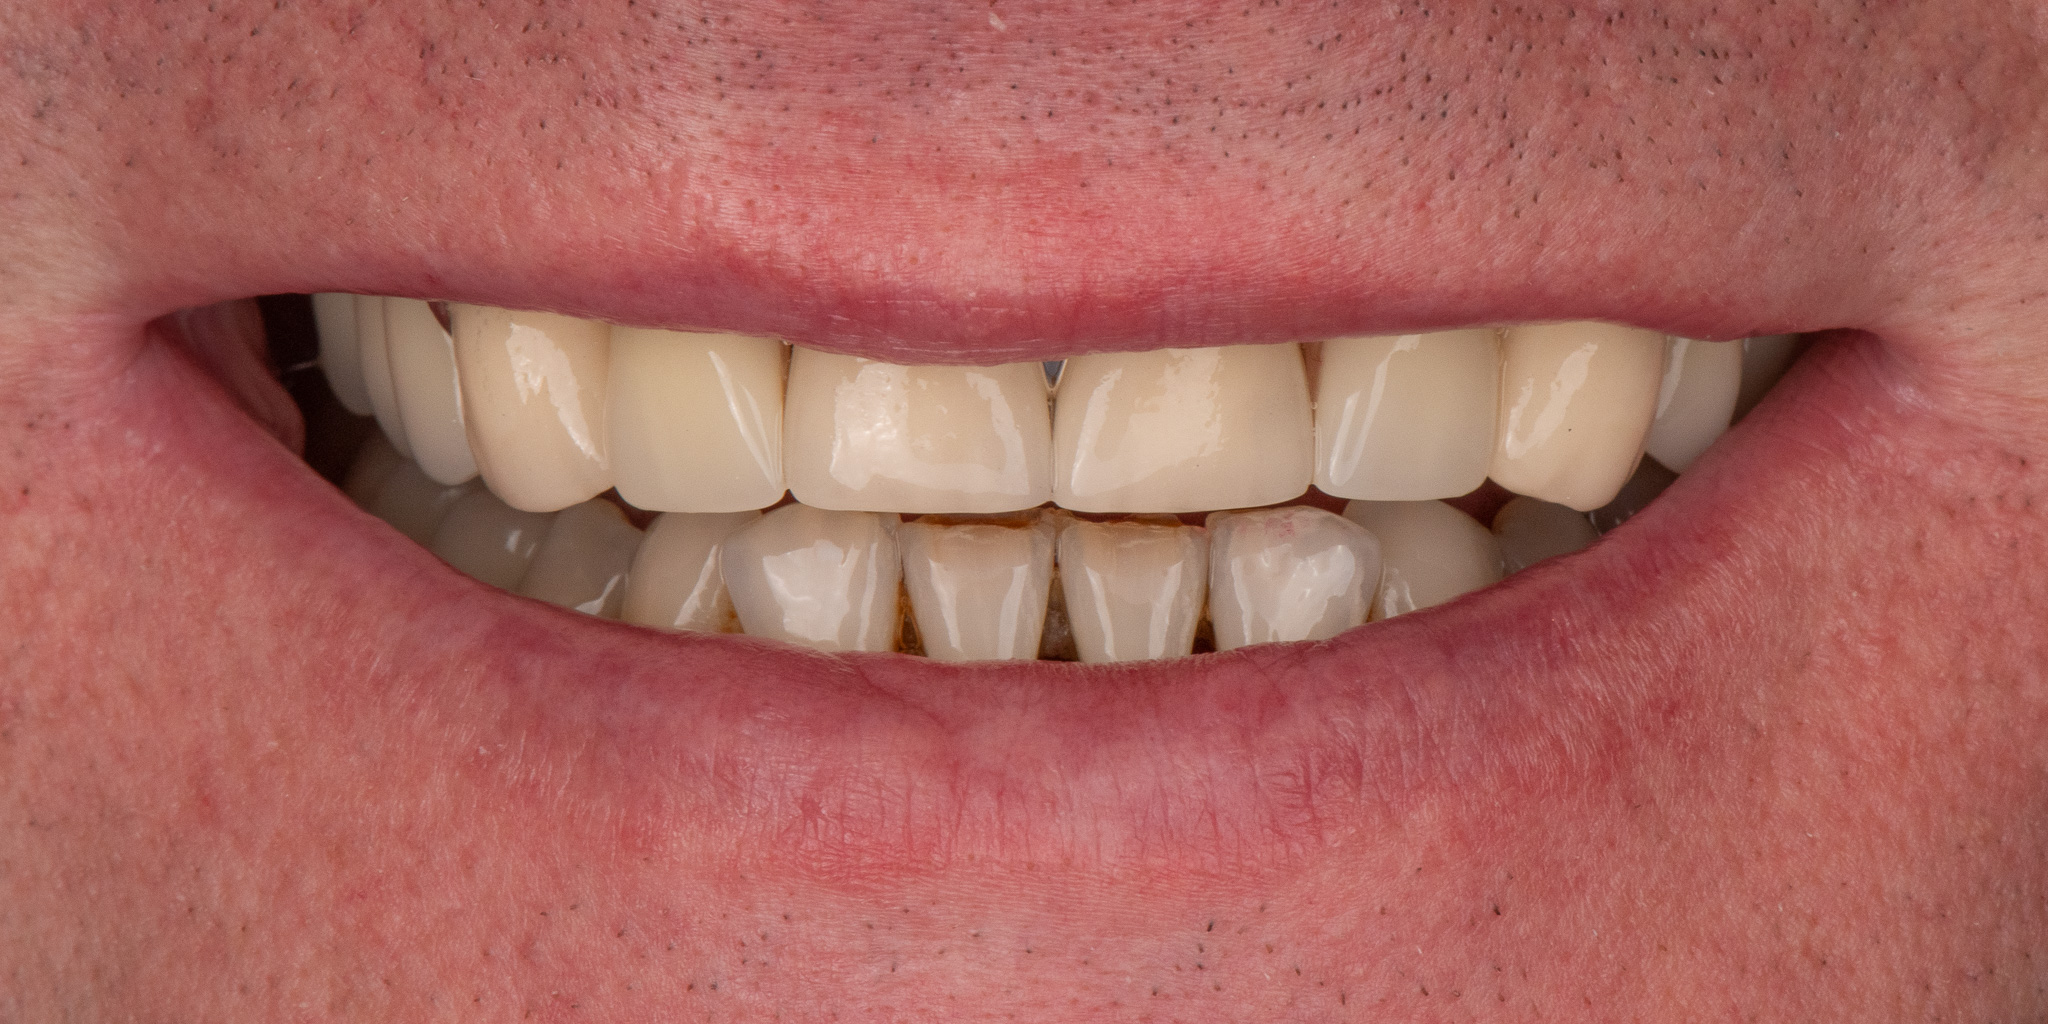

Pacjent 2

Pacjent zgłosił się w celu poprawy estetyki uzębienia, oraz wymiany użytkowanego od lat mostu protetycznego

Zaplanowane leczenie obejmowało wykonanie nowych koron pełnoceramicznych na podbudowie cyrkonowej na zęby górne oraz bezklamrowej protezy szkieletowe na zatrzaskach - rozwiązanie zapewniające wysoki komfort żucia oraz estetykę uśmiechu - brak widocznych elementów protezy na zębach własnych pacjenta.